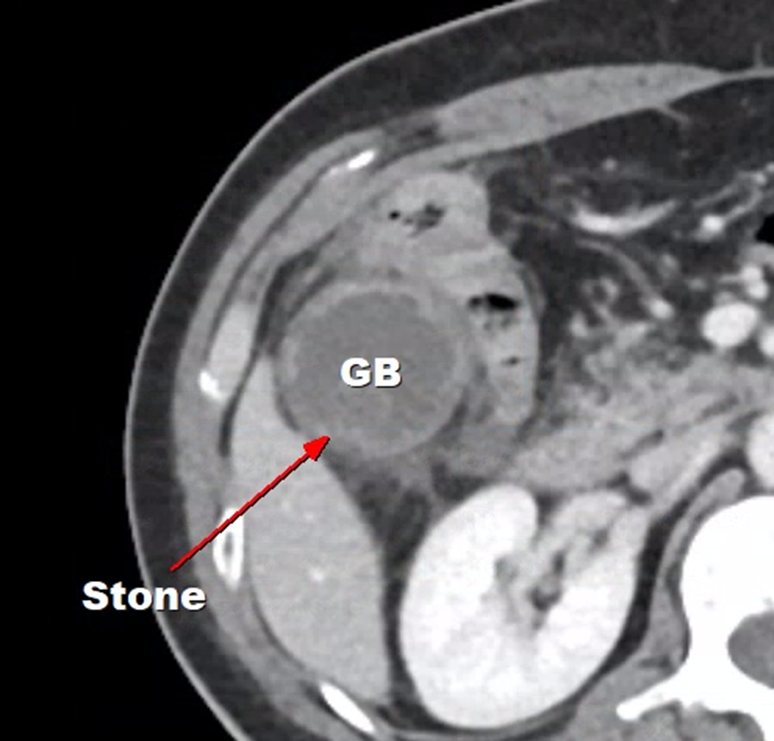

- 담석이 있는 급성 담낭염

담석이 있는 급성 담낭염의 경우 수술적으로 담낭을 제거를 해줘야 하는데요. 환자의 전신 상태가 좋지 않거나 노령이라 응급 수술을 하기 어려운 경우 시간을 벌 목적으로 경피적담낭배액술을 합니다. 그렇게 시간을 번 뒤 환자분의 컨디션이 안정적으로 변하면 수술을 하는 거죠.